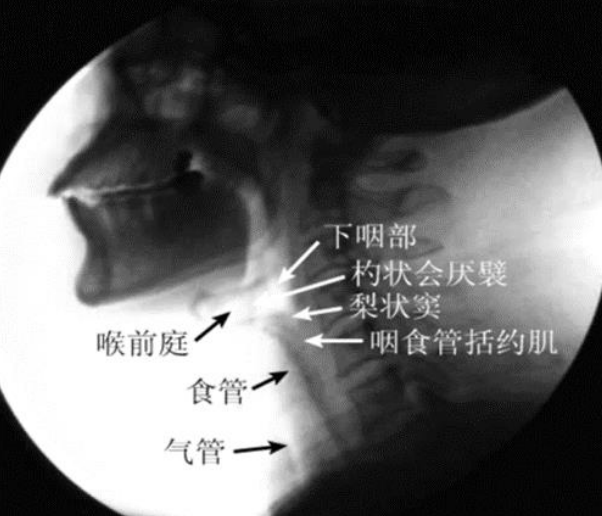

经过多年的努力与发展,目前我们医院拥有专业的吞咽治疗室及吞咽治疗师,能够完成吞咽相关评估及治疗,其中吞咽造影检查(VFSS)是检查吞咽功能最常用的方法,是吞咽障碍检查和诊断的“金标准”,我科与我院影像科合作开展,其在X线透视下,针对口、咽、喉、食管的吞咽运动所进行的特殊造影,其可视化特点有利于观察吞咽过程各个时期的特点,主要包括:

(1)口腔期

(2)咽期、食管期